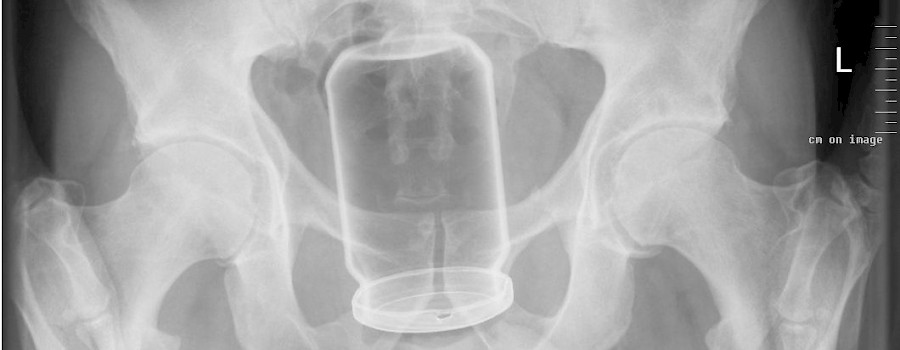

Fremdkörper in Anus und Rektum

rockpop 30 Nov, 2018 00:00

Ein Fremdkörper in Anus und Rektum, häufig auch rektaler Fremdkörper genannt, ist ein meist durch den After in den Mastdarm (Rektum bzw. lat. Rectum) eingeführter und dort befindlicher Gegenstand.